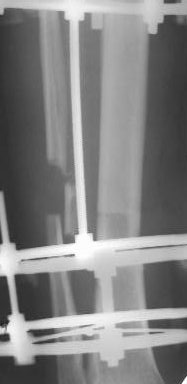

Когда уважаемый д-р Джолдас Кульджанов демонстрировал снимки закрытия раны на голени, у меня лечился больной по поводу открытого переломаголени в н/3 (3Б по Каплану), после вторичной обработки и стабилизации перелома АВФ, нанесены послабляющие разрезы кожи, оставался поперечный дефект кожи голени.

Решил использовать методику резиновой стяжки для закрытия дефекта. Рану разделил на две части . Одну часть стягивал с помощью скобок. Изготовил скобки из спиц 2мм. Скобками зацепил края раны, к скобкам привязал резиновые стяжки, которые фиксировал на деталях аппарата. Рана закрылась в течение 4х дней. Наложил вторичные швы.

Другую часть стягивал с помощью П-образных швов через резиновые трубки. В течение суток П-образные швы снял из-за угрозы прогрессирования некроза. На 4 день начал стягивать этот участок раны с помощью скобок и резиновой стяжки. Рана закрылась через 3 дня, наложил вторичные швы на этот участок. Метод понравился. Возникли вопросы.